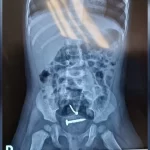

Criança que era estuprada pelo pai tem parafusos dentro do corpo, aponta exame

Exames reveleram que, além de lesões nas partes íntimas, a menina tinha parafusos dentro do corpo